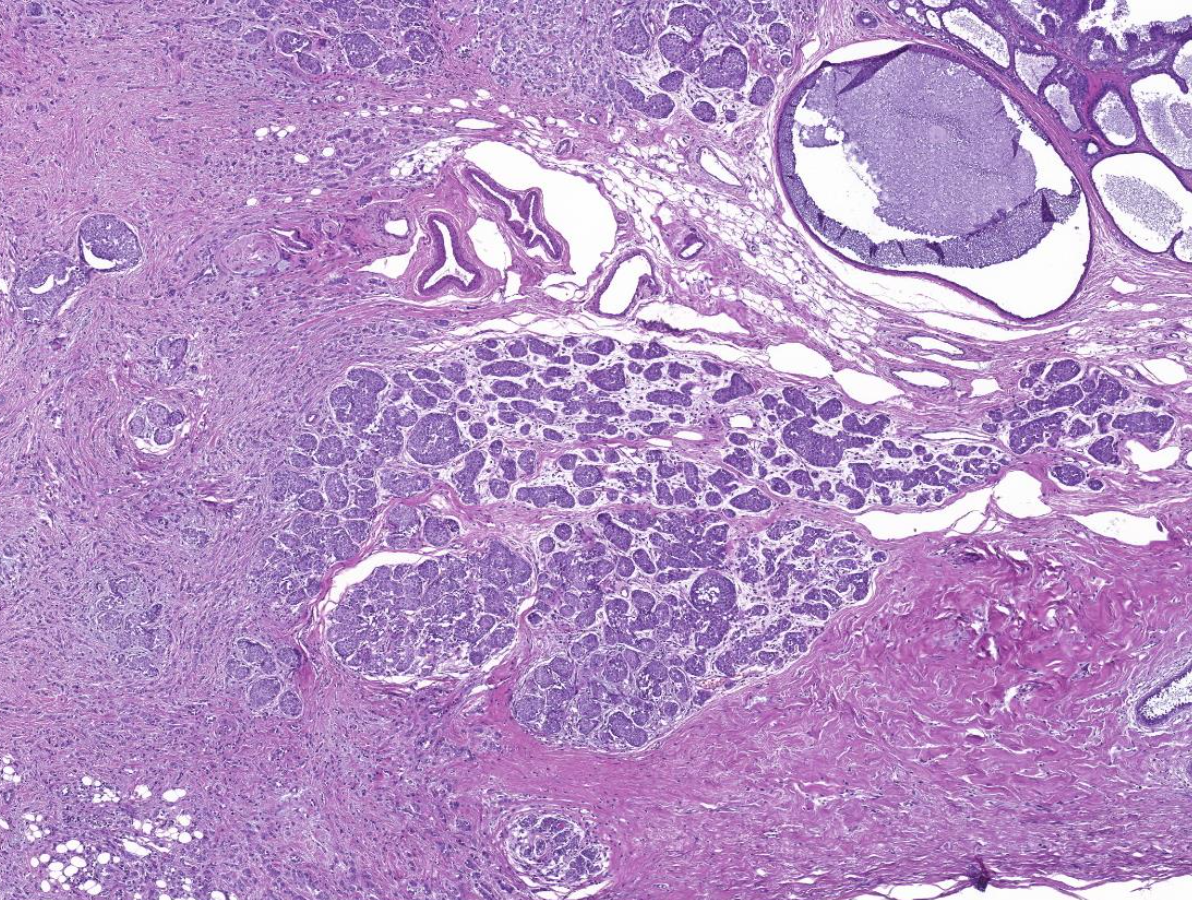

Diagnose?

Invasives unspezifisches duktales Mamma-CA